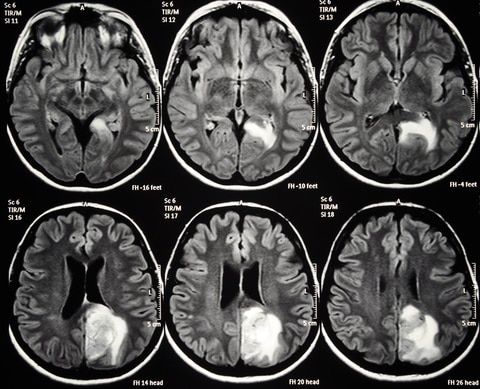

Brain MRI Image Classifier

Upload a Brain MRI Image and get it classified according to Tumour Type.